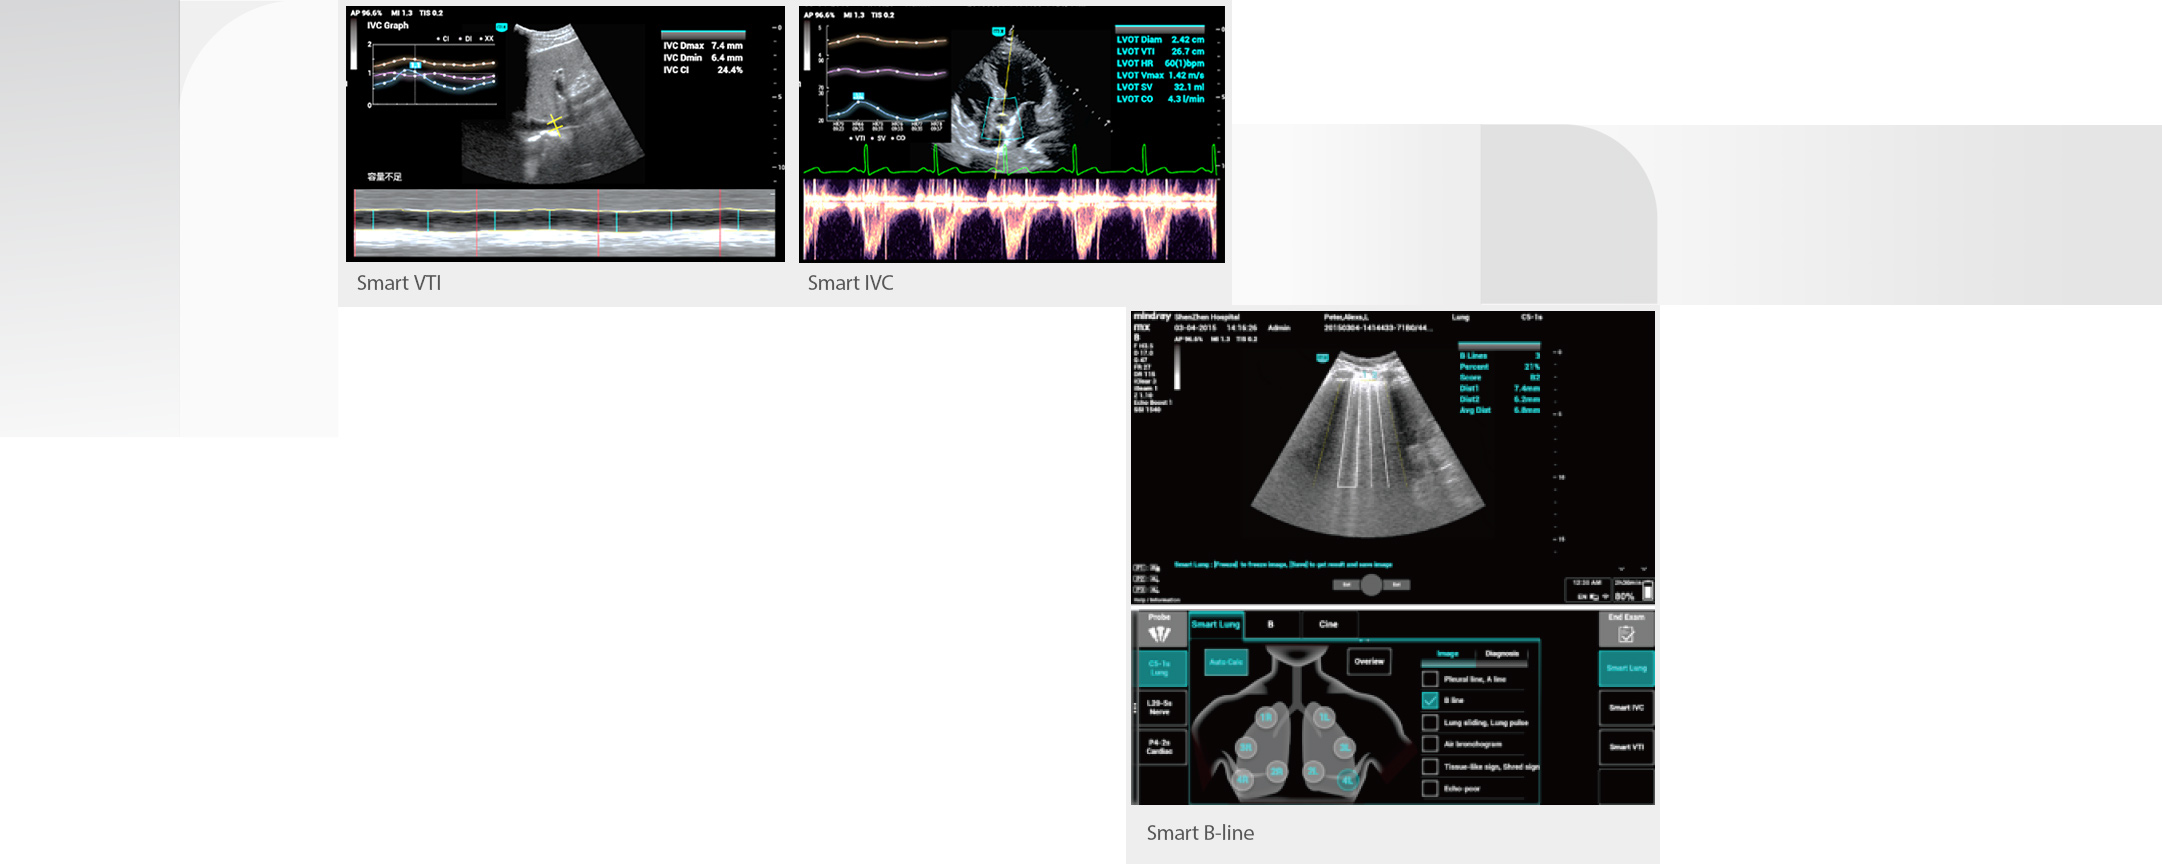

Pati?nten op de intensive care hebben meestal cardiopulmonale, lever- en nierinsuffici?ntie of -falen, en hun vitale functies kunnen op elk moment veranderen, waarbij de lichaamsvloeistoffen bij ongeveer 90% van de ernstig zieke pati?nten snel veranderen. Gastro-intestinale bloeding, ernstige endocriene en metabole stoornissen, verstoringen van het water-elektrolyten- en zuur-base-evenwicht, lever- en nierdisfunctie zijn allemaal veel voorkomende afwijkingen op de IC die tot uiting komen in veranderingen in de lichaamsvloeistoffen.

Daarom zijn nauwgezette vloeistofmonitoring en nauwkeurig volumebeheer van pati?nten van het grootste belang. Echografie heeft echter het voordeel dat het intu?tiever is bij de dynamische beoordeling van de cardiopulmonale functie en de hemodynamiek van pati?nten, en kan IC-medewerkers helpen bij het nemen van tijdige beslissingen over de behandeling en bij het waarnemen van de effecten van de behandeling in realtime.

Daarom zijn nauwgezette vloeistofmonitoring en nauwkeurig volumebeheer van pati?nten van het grootste belang. Echografie heeft echter het voordeel dat het intu?tiever is bij de dynamische beoordeling van de cardiopulmonale functie en de hemodynamiek van pati?nten, en kan IC-medewerkers helpen bij het nemen van tijdige beslissingen over de behandeling en bij het waarnemen van de effecten van de behandeling in realtime.